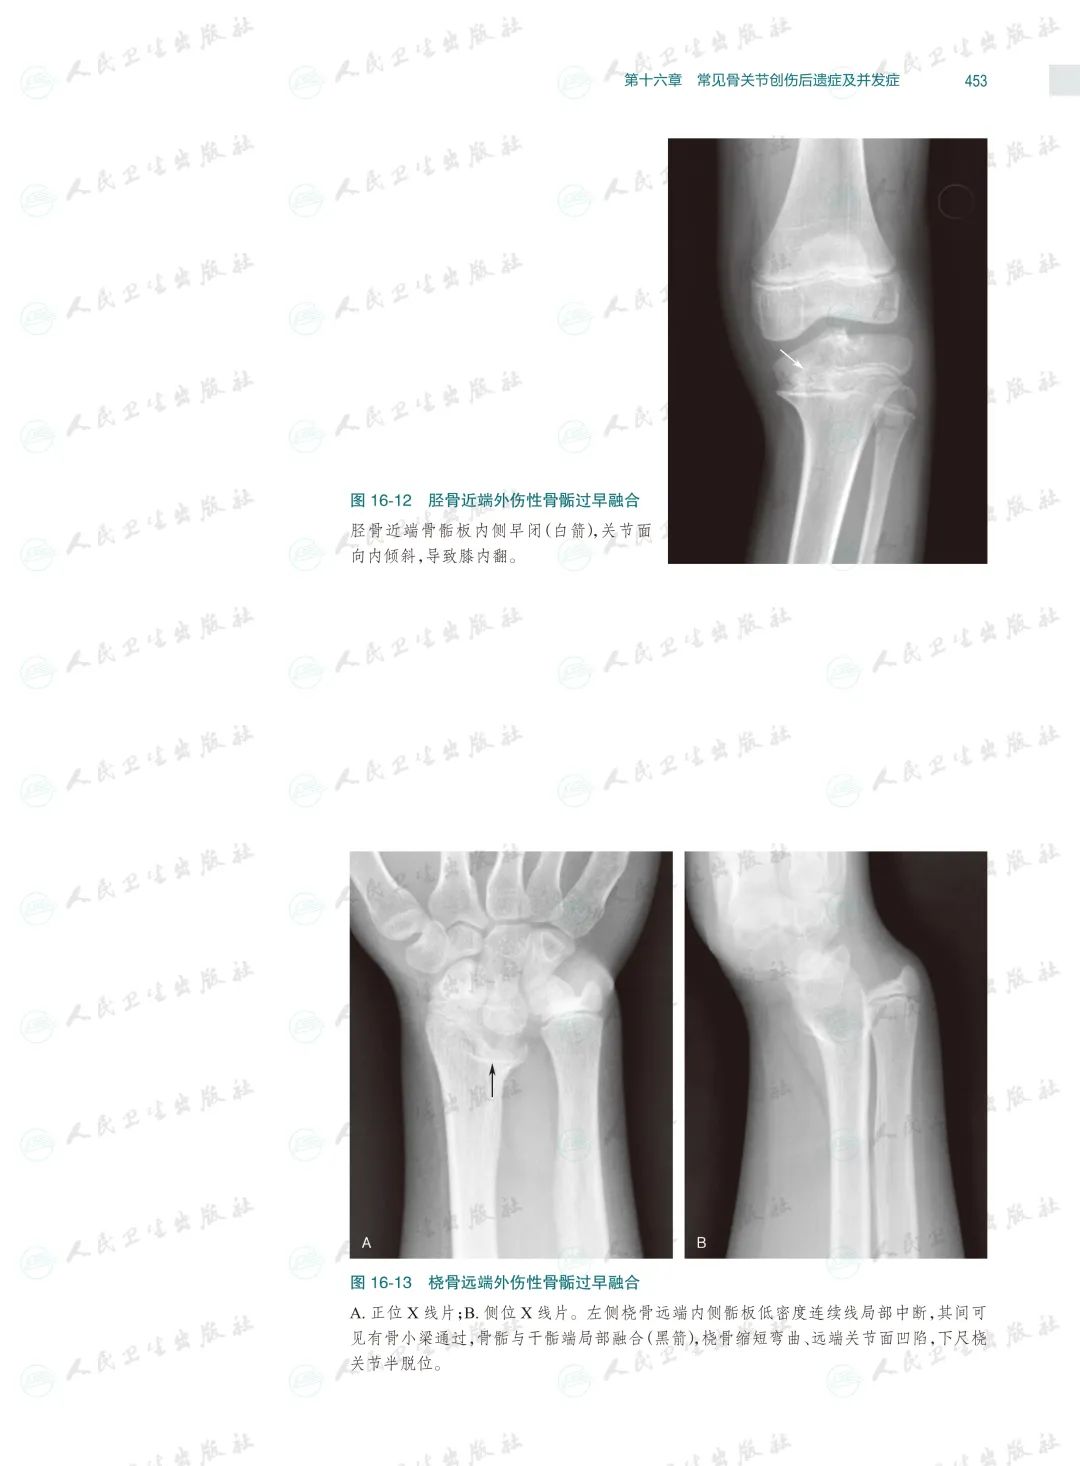

骨关节创伤是骨科临床常见病,X线检查是其最基本和最常用的检查方法。本书以临床典型病例X线检查资料为素材编写,已是第4版了,一直以来本书都因为其实用性而深受读者的喜爱,本次修订根据近几年骨关节创伤领域的#新进展,对目录进行了重新编排、对过时内容进行了修改、对清晰度和对比度欠佳的图片进行了替换,同时还充实了10多个病种的病例图片,并新增了常见骨关节创伤后遗症及并发症章节。

本书以图片展示为主,内容丰富,几乎包括了除头面部以外各个部位的骨关节创伤类型,图片清晰且有详细文字注解,每一章节的创伤类型、诊断要点和鉴别诊断均作了简要叙述。由于图片都是来自作者日常工作的资料积累,因此实用性较强,是一本不可多得的参考书。

本书在第3版基础上修订而成,是一本系统全面介绍骨关节创伤X线诊断的图谱专著。全书共十六章,前十五章每章基本按创伤类型、诊断要点和鉴别诊断体例编写,最后一章介绍常见骨关节创伤后遗症及并发症。书中共选用1270幅X线照片图,约760个病例,所选图片和病例均具有代表性,可使读者对各部位、各类型的骨关节创伤及其后遗症和并发症有进一步认识,从而提高诊断水平。本书主要供骨科医生、影像科医生及医学院校相应专业的学生使用。